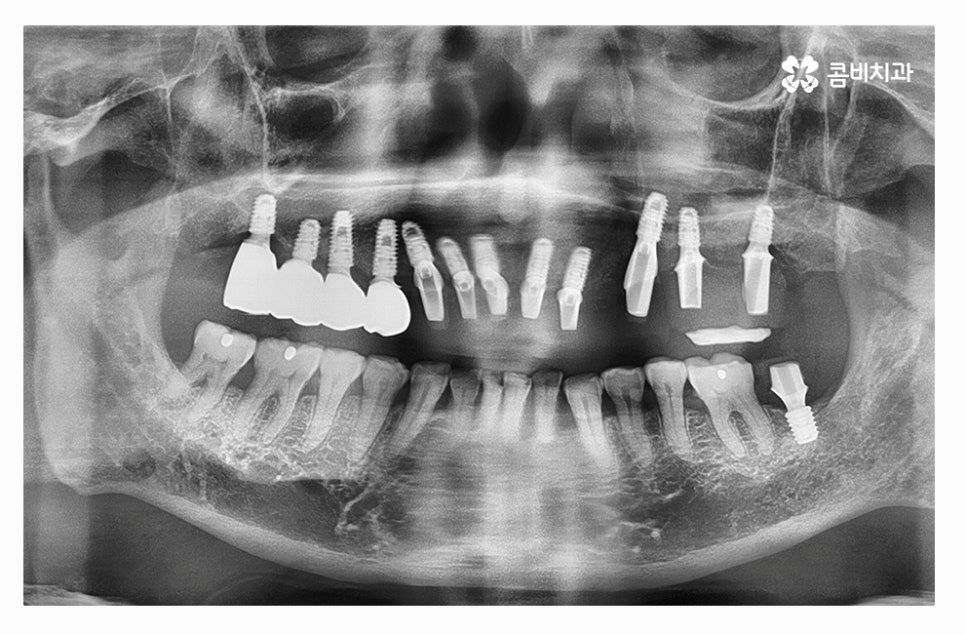

전체임플란트의 장점은 자연치아의 심미성과 매우 흡사하며

수명이 길고 저작력이 자연치아와 거의 비슷하다는 장점이 있지만

치료를 안전하게 마무리하고 수명을 오랫동안

건강하게 유지하는 것이 무엇보다 중요하다고 할 수 있는데요

임플란트의 치료 기간은 개개인의 잇몸과 구강 상태 등에 따라

다르며 임플란트와 잇몸 뼈가 튼튼하게 결합이 돼야 하기 때문에